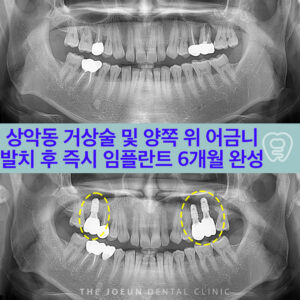

호산동치과

호산동치과 발치 후 즉시 임플란트 식립 6개월 완성

호산동치과 발치 후 즉시 임플란트 식립 6개월 완성   임플란트를 고려하는 분들 중 위턱, 특히 어금니 부위에 식립이 필요한 경우 치료가 쉽지 않다고 느끼는 경우가 많은데요. 이 부위는 해부학적으로 상악동이라는 공간이 존재하는데 이 구조가 임플란트 식립을 어렵게 만드는 원인이 되기도 합니다. 상악동은 코 옆쪽 볼뼈 아래 위치한 공기로 채워진 공간으로 더보기…